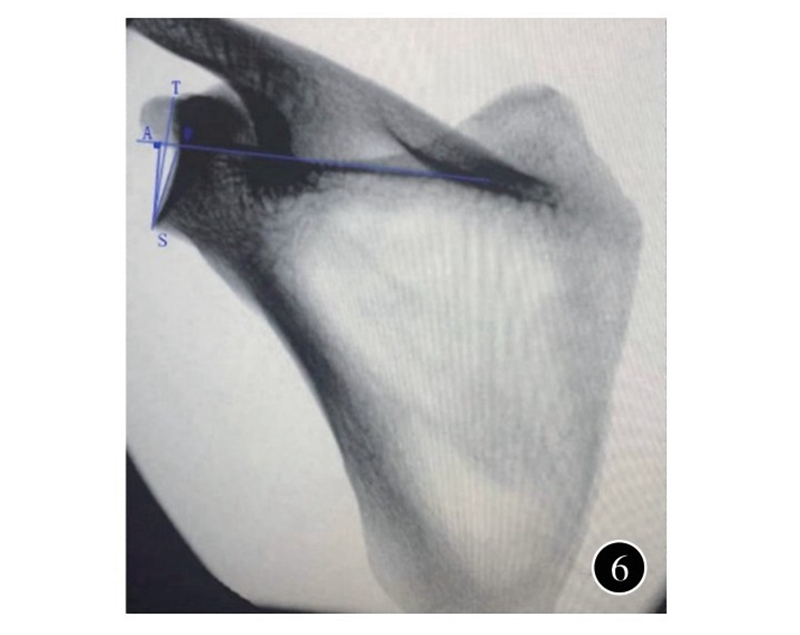

一般认为,肩胛盂关节面有5~7°的向上倾斜;但由于肩胛骨的位置和解剖的不规则,很难准确描述测量标准。在肩胛骨骨折中,有人用盂极角(glenopolar angle,GPA) 来描述肩胛盂倾斜的变化;但其为间接测量,应用也局限。有人用肩胛盂最高点至最低点的连线,与冈上窝底的夹角来评估肩胛盂向上的倾斜,也被称为β角,代表了肩胛盂整体在冠状面的倾斜程度,在肩胛骨正位X线和三维CT测量中具有极佳的准确性和可重复性。更进一步,肩胛盂最高点至最低点的连线与冈上窝底垂线的夹角被称为全肩关节成形角(total shoulder arthroplasty angle,TSA角) ,与β角互为余角,同样用于评估肩胛盂向上的倾斜(图6) 。根据其倾斜的方向,又分为向上倾斜和向下倾斜,代表肩胛盂的 倾斜程度,在肩关节成形术前规划中较为重要。肩胛骨前后位X线、二维CT和三维CT均被用于测量肩胛盂在冠状面上的倾斜,但以三维CT测量所得数据最为精确。肩关节退变患者TSA角的测量均值为7.68~12°;正常人群TSA角为2~5.3°。在反肩关节成型术中,基座一般放置在肩胛盂下部,因而Boileau等提出了反肩关节成型角 (reverse shoulder arthroplasty angle,RSA角) (图6) ,即肩胛盂下部连线与冈上窝底垂线之间的夹角,能更加精确评估肩胛盂下部形态。他们测量肩关节退变患者RSA 角的测量为20°,较TSA角大8°。骨性关节炎、肩胛盂磨损行肩关节成型术前需行三维CT重建用于测量肩胛盂磨损导致的肩胛盂倾斜的改变,精准评估肩胛盂情况。

图6 肩胛骨正位X线用于测量肩胛盂向上倾斜的示意图。全肩关节成形角为肩胛盂最高点至最低点的连线与冈上窝底垂线的夹角;反肩关节成型角为肩胛盂下部连线与冈上窝底垂线之间的夹角